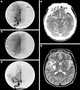

The leptomeningeal collateral circulation (also known as leptomeningeal anastomoses or pial collaterals) is a network of small blood vessels in the brain that connects branches of the middle, anterior and posterior cerebral arteries (MCA, ACA, and PCA), with variation in its precise anatomy between individuals. During a stroke, leptomeningeal collateral vessels allow limited blood flow when other, larger blood vessels provide inadequate blood supply to a part of the brain. [Source: Wikipedia ]